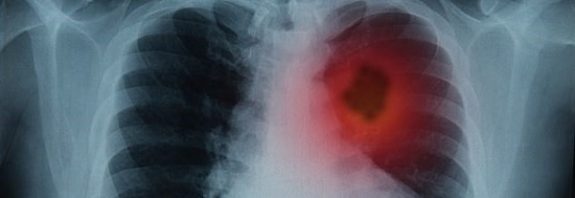

Bilim İnsanları Kanserli Hücrelerin Metastazını Durdurabilecek Bir Atılım Keşfetti

Bilim İnsanları Kanserli Hücrelerin Metastazını Durdurabilecek Bir Atılım Keşfetti Uzmanlara göre kanserin nasıl yayıldığını anlamak daha iyi tedavilere yol açacak … Bilim İnsanları Kanserli Hücrelerin Metastazını Durdurabilecek Bir Atılım Keşfetti okumayı sürdür